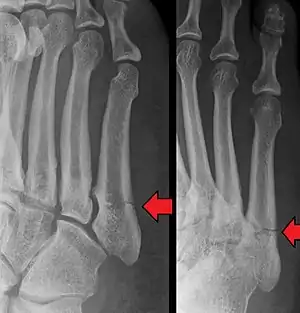

Diagnosis

A person with a Jones fracture may not realize that a fracture has occurred. Diagnosis includes the palpation of an intact fibularis (peroneus) brevis tendon, and demonstration of local tenderness distal to the tuberosity of the fifth metatarsal, and localized over the shaft of the proximal metatarsal.

Diagnostic x-rays include anteroposterior, oblique, and lateral views and should be made with the foot in full flexion.

Other proximal fifth metatarsal fractures exist, although they are not as problematic as a Jones fracture. If the fracture enters the intermetatarsal joint, it is a Jones fracture. If, however, it enters the tarsometatarsal joint, then it is likely an avulsion fracture caused by pull from the fibularis (peroneus) brevis tendon. An avulsion fracture at the base of the fifth metatarsal is sometimes called a "dancer's fracture" or a "pseudo Jones fracture", and usually responds readily to non-operative treatment.[18] The x-ray appearance of the developmental "apophysis" in this area may have some resemblance of a fracture, but is not a fracture; it is the secondary ossification center of the metatarsal bone. It is a normal finding that occurs at this site in adolescents.[19] If an injury to that area has occurred, the physician is often able to interpret certain radiographic clues to make the differentiation. An avulsion fracture at this location is typically extra-articular and oriented transversally as compared to the longitudinal orientation of an unfused apophysis.[19]